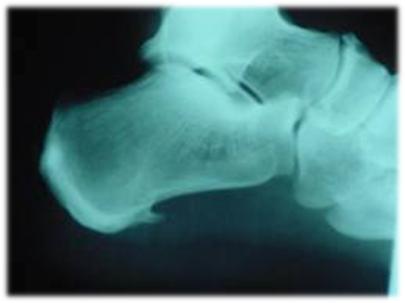

Espolón calcáneo

Una causa frecuente de dolor de talón es el espolón, un crecimiento óseo en la parte inferior del hueso del talón. El espolón, visible con rayos X, aparece como una prolongación que puede extenderse hasta 1 ó 2 cms. Cuando no hay indicación de crecimiento del hueso, a veces se llama a esta condición "síndrome de espolón del talón".

Los espolones resultan de un esfuerzo excesivo de los músculos y ligamentos del pie, que estira la banda de tejido que conecta el talón y la parte anterior del pie, y arranca repetidamente la membrana que cubre el hueso del talón. Esta condición puede ser resultado de un desequilibrio biomecánico, de correr, de zapatos inapropiados o demasiado gastados, o de obesidad.

Esta lesión suele tratarse con éxito mediante el uso de plantillas ortopédicas que alivian la tensión sobre la zona haciendo que los movimientos sean menos dolorosos. Los ejercicios de estiramientos también son efectivos para eliminar o disminuir el dolor. En caso de que aparezcan inflamaciones, se pueden tratar mediante infiltraciones de fármacos antiinflamatorios.